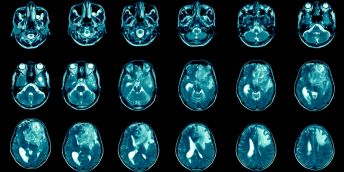

The number of people living with atrial fibrillation – a dangerous heart condition and major cause of stroke – has increased by 72% in England over the last two decades, according to new research.